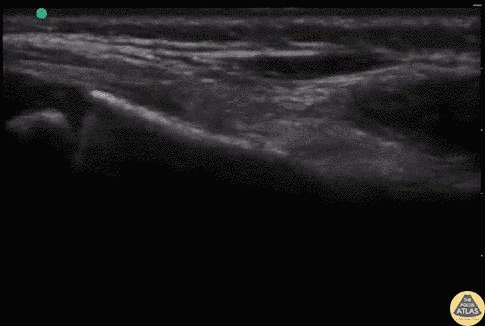

Pediatrics - Radius Fracture (Distal)

7 year old fallen off monkey bars. Tender over right distal radius with mild swelling. POCUS reveals a discontinuity in the hyperechoic cortex of the child's distal radius with minimal displacement. This is suggestive of a buckle fracture or minimally displaced distal radius fracture. Dr. Sathya Subramaniam, Pediatric EM Fellow - Kings County/SUNY Downstate